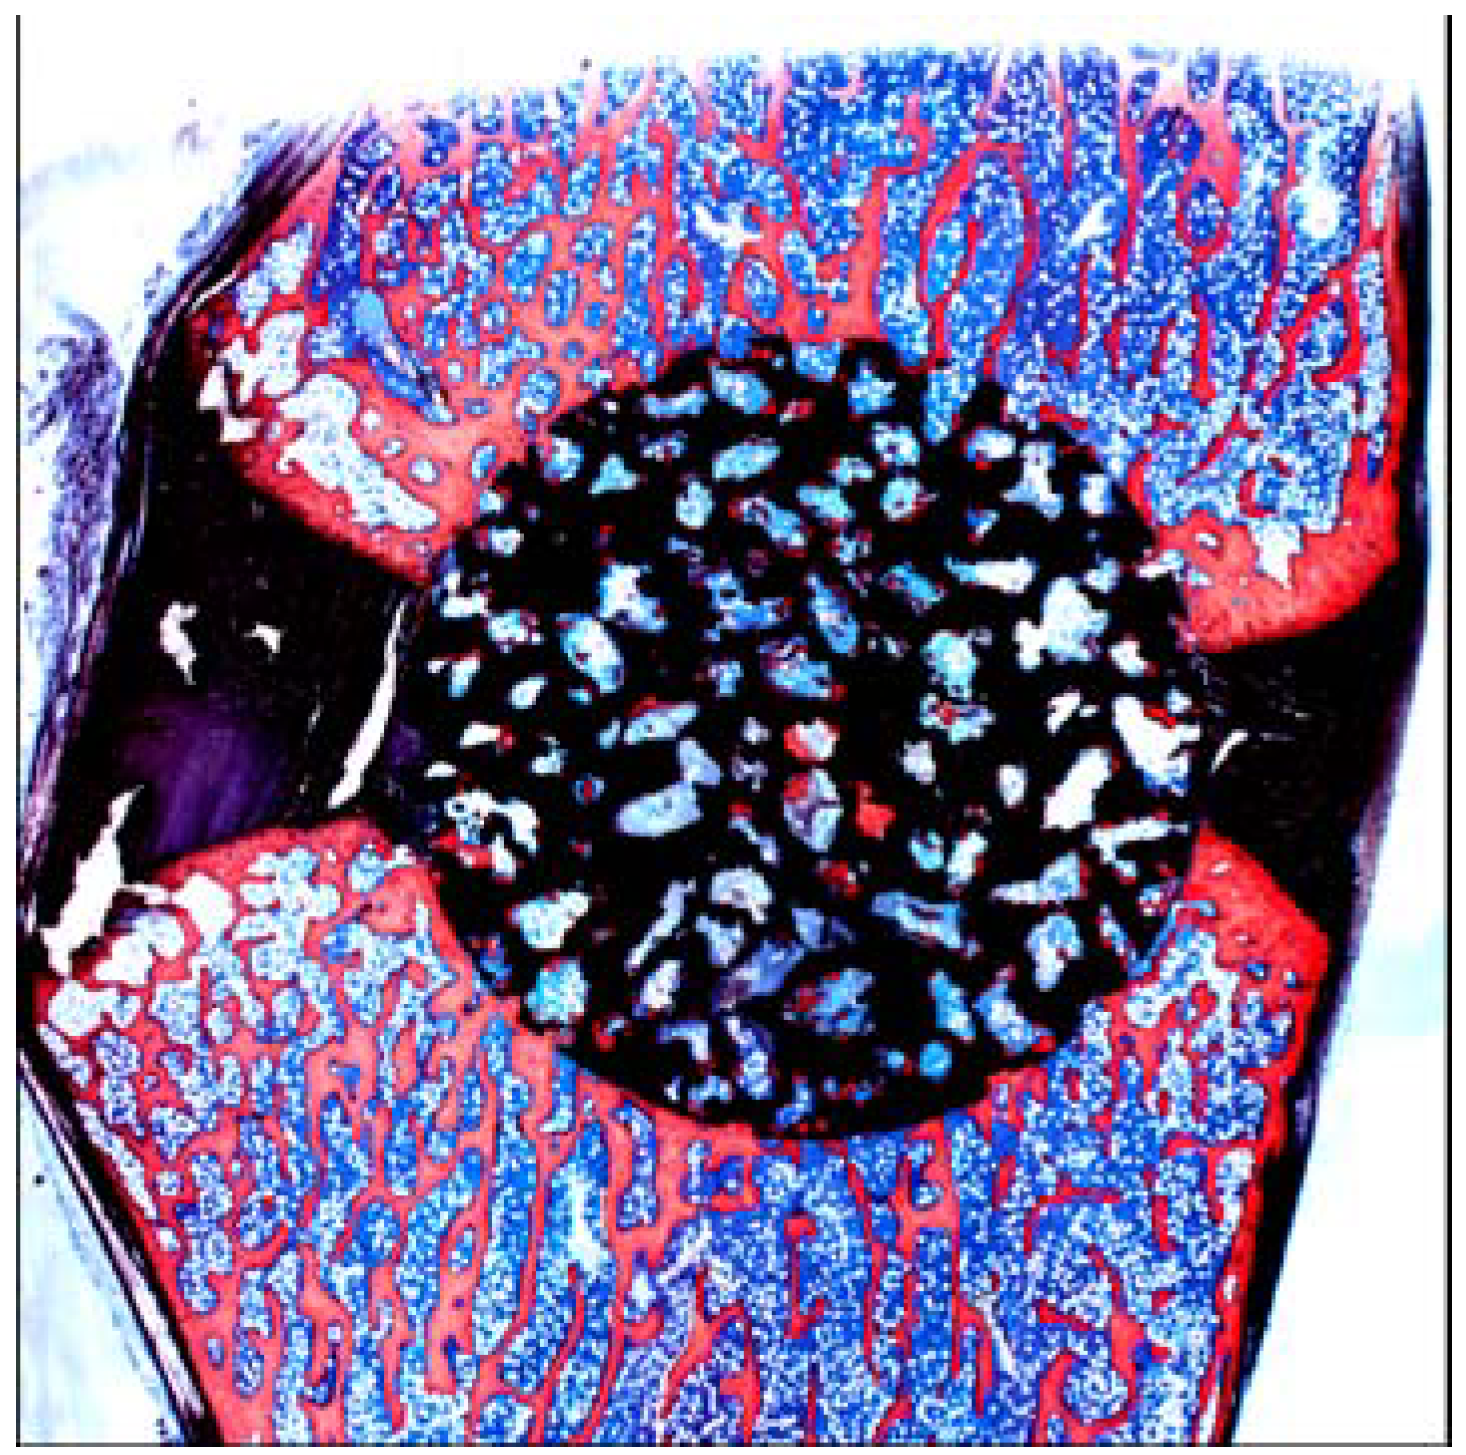

A porous Ti metal sample containing 50 to 70 vol % of interconnected pores 200–500 μm in diameter was subjected to NaOH, 0.5 mM HCl, and heat treatments to form titanium oxide on its pore walls. The thus-treated porous Ti metal was fully penetrated with newly grown bone from its periphery when it was implanted into the femur of a rabbit, as shown in Figure 21 [19]. This porous Ti metal formed bone tissue from its centre when it was implanted into the muscle of a dog, as shown in Figure 22 [20]. These results indicate that the thus-treated porous Ti metal exhibits osteoinductivity, as well as osteoconductivity. This was successfully applied to a spinal fusion device of a dog, as shown in Figure 23 [21], and is subject to clinical tests for a human device.

Figure 22.

Bone formation in porous Ti metal subjected to NaOH, HCl and heat treatments, 3 and 12 months after implantation into muscle of beagle dog. Stain: Stevenel’s blue and Van Gieson’s picrofuchsin. Reprinted from Ref. [20] with permission from Elsevier.